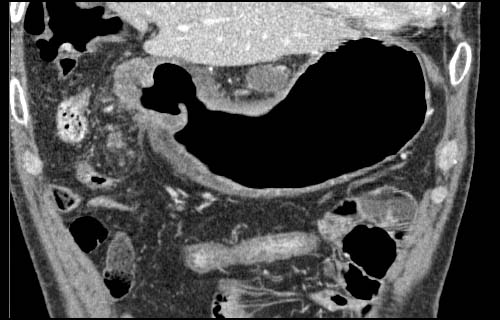

Gastric cancer / Borr.III

Coronal MPR